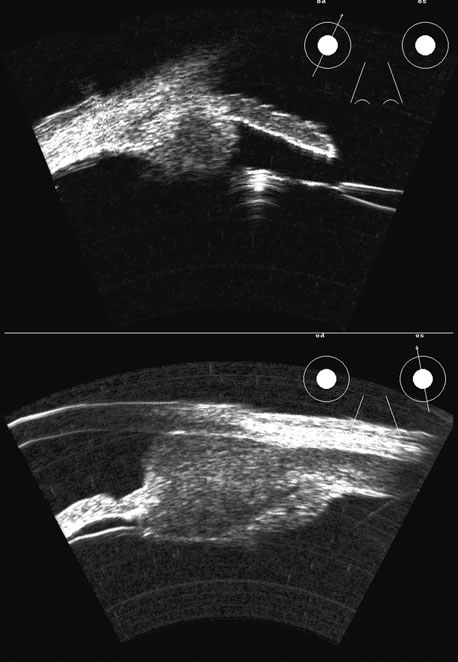

There are several tumors that invade the vitreous or the vitreous space. In

children, retinoblastoma can seed the vitreous; in adults, reticulum

cell sarcoma can cause vitreous clouding but is nondiscernible from

other forms of debris. A very high percentage of retinoblastomas contain

calcium, which is very reflective (Fig. 20). Malignant melanoma, hemangioma, metastatic carcinoma, and subretinal

hemorrhage can all present with elevated convex lesions that protrude

or extend into the vitreous space and are the four most commonly

seen posterior segment tumors. Anteriorly, medulloepithelioma (diktyoma) and

melanocytoma or ciliary body cysts can also protrude

into the vitreous. The differentiation of these tumors has been well

described with conventional combined B- and A-scan ultrasound

techniques2 and standardized A-scan echography,28 as well as more modern spectral analysis techniques. These all provide

excellent means of differentiating solid from cystic lesions, but differentiation

between diktyoma (medulloepithelioma), melanocytoma, and

melanoma is not possible with A-scan or B-scan.

Malignant melanoma varies in its ultrasound presentation from a relatively homogeneous to heterogenous lesion on B-scan. The typical uveal melanoma absorbs sound so that the posterior section is relatively less echoic than the anterior aspect, producing a gradually decreasing amplitude, often to baseline on the A-scan (Fig. 21).

Melanomas also have varying amounts of melanin, a highly acoustically reflective pigment. As noted, melanomas characteristically show high reflectivity anteriorly, with decreasing reflectance as the sound traverses the tissue. This produces the decreasing amplitude posteriorly in the tumor seen on A-scan and gray-scale B-scan. This effect often enhances the anterior scleral boundary. The posterior tumor border is thus measured as the first “rising” echo from the tumor decline, and it is most easily seen and accurately identified on B-scan.27 Metastatic carcinoma is more heterogeneous, producing a more uniform A-scan amplitude of roughly 50% to 80% of the “scleral” echo amplitude (see below) behind the tumor (Fig. 22). Hemangioma is a very highly reflective tumor with high amplitude all the way through the tumor of 80% to 100% of scleral echo amplitude (Fig. 23). The differentiation of tumor tissues is made possible by differences in cellular organization and concentration.29 Acoustically, these are termed as differences in backscattering properties.30–32 A homogeneous solid tissue, such as the lens or the optic nerve, may present few or no echogenic discontinuities and thus appear anechoic and cyst-like. (An echogenic discontinuity is technically an acoustic impedance mismatch in which the acoustic impedance is the product of the density and the speed of sound in each tissue.) A fluid–smooth tissue boundary has a high mismatch or discontinuity and thus produces a high-amplitude echo. A hemangioma with alternating blood- and tissue-lined sacs thus produces a solid-appearing tissue with high-amplitude echoes seen at all depths of the tissue. A metastatic tumor is nearly always a very heterogeneous tissue with randomly organized clumps of similar cells bounded by strands of vessels, necrotic areas, and connective tissue, thus producing a pattern of moderately high-amplitude sustained echoes. To provide a meaningful, reproducible standard of comparison, we use the scleral echo—that is, an echo behind the tumor—for comparison. We believe that the scleral echo generally is highest at the posterior sclera–Tenon's boundary; whereas Ossoinig has stated that the high amplitude echo is at the anterior scleral boundary.28,33 This school (standardized echography) also recommends a tissue velocity for melanoma of 1550 m/sec34,35 compared with the value of 1660 m/sec that we recommend. These differences can produce significant variations in measurement of tumor height, depending on the interpretive methodology used. The velocity of 1550 m/sec gives a smaller tumor height than that of 1660 m/sec, wheras the inclusion of scleral thickness may add 1 to 2 mm to the tumor height when standard echography is used. While this does not affect comparisons of tumor growth, it has a significant bearing on comparisons of data from various investigators.27 On B-scan, the invasion or replacement of the choroid by tumor is of diagnostic importance. Subretinal hemorrhage rests on a smooth curve of the posterior poles; whereas melanoma may replace the choroid, producing an “excavated” pattern.36 A completely dislocated lens can also emulate a tumor but can be differentiated by clinical findings and by having the patient move his or her eye during the examination, which causes lens displacement (Fig. 24).